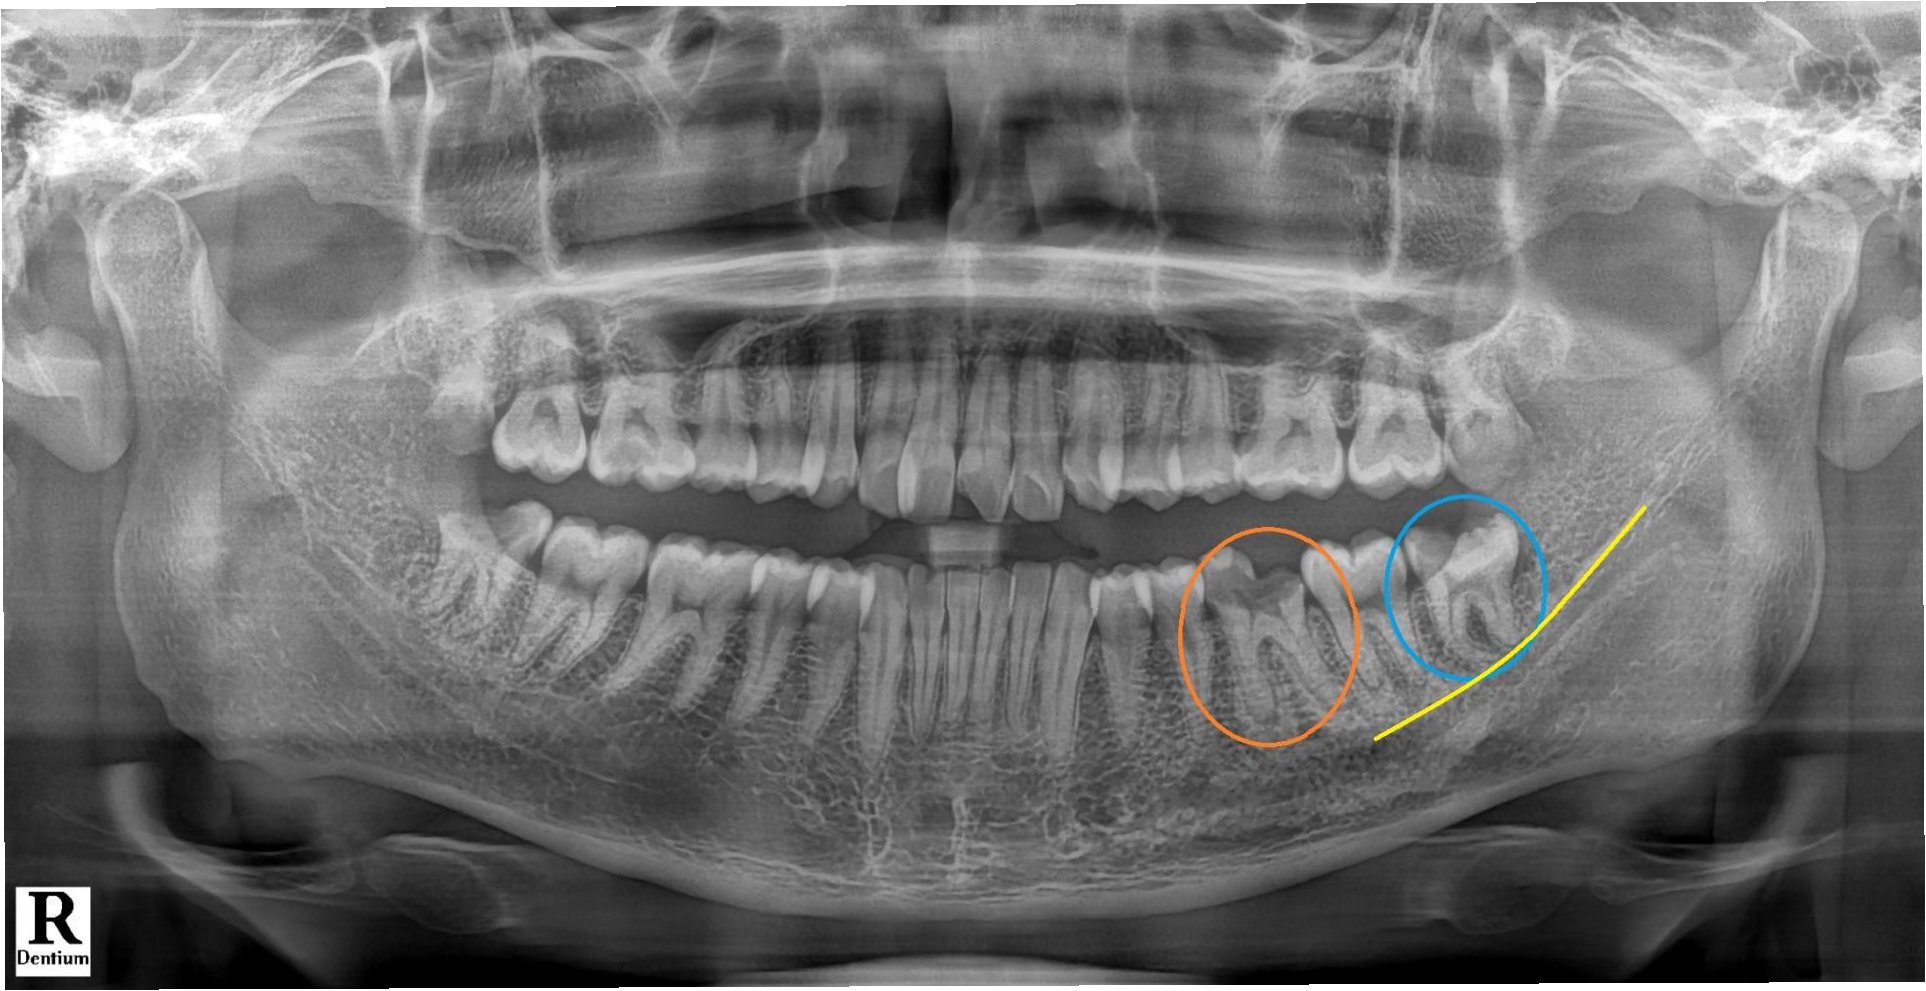

어금니 끝, 잇몸 깊숙한 부위의 통증은 사랑니가 나는 과정에서 생긴 염증일 수 있습니다. 사랑니는 17~25세 무렵 자라며, 턱뼈가 작아진 현대인에겐 비정상적인 위치에 나는 경우가 많습니다. 대부분 가장 안쪽에 위치해 양치가 어려워 충치와 염증에 취약합니다. 일부만 나왔을 때는 잇몸에 염증이 생겨 고름이 나오는 '치관주위염'이 되기도 합니다.

사랑니 발치 시기와 주의사항

사랑니는 염증이나 충치가 심하지 않으면 보존 치료로 관리할 수 있지만, 염증이 반복되거나 충치가 심하면 발치를 고려해야 합니다. 나이가 들수록 뼈가 단단해져 수술이 어려워지므로, 발치는 보통 20세 전후가 적기입니다. 또한 발치 후에는 감염 등 후유증을 막기 위해 치과의 주의사항을 잘 지켜야 합니다.